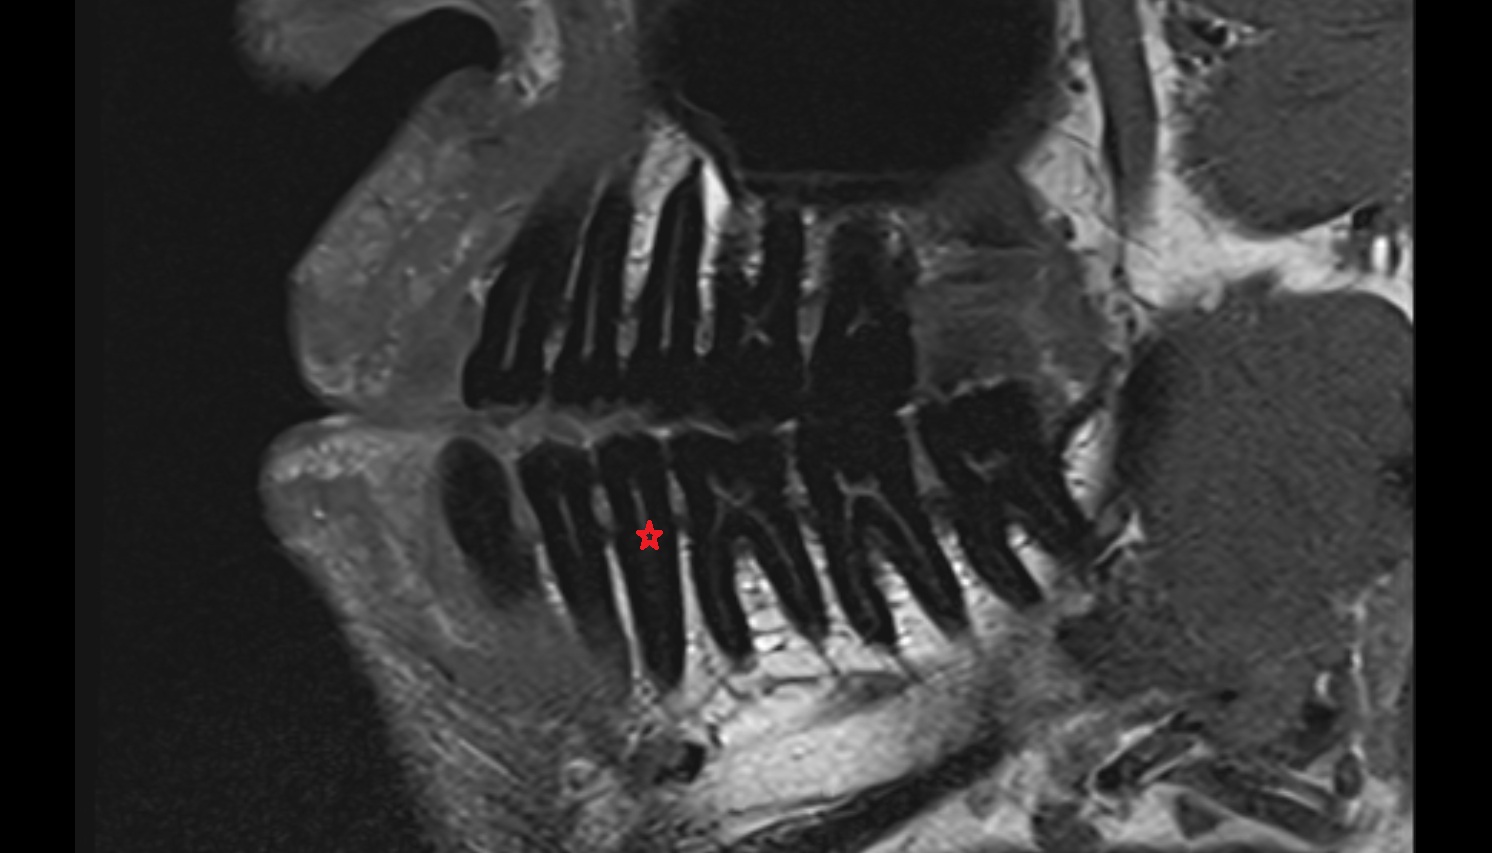

- Central inferior incisor tooth

- Central superior incisor tooth

- Inferior canine tooth

- Lateral inferior incisor tooth

- Lateral superior incisor tooth

- superior canine tooth

- Superior first molar tooth

- Superior first premolar tooth

- Superior second molar tooth

- Superior second premolar tooth

- Superior third molar tooth

- Inferior first premolar tooth

- Inferior second molar tooth

- Inferior second premolar tooth

- Inferior third molar tooth

- Root of lower molar tooth

- Root of upper molar tooth

- Root canal of upper molar tooth

- Dental pulp of upper molar tooth

- Enamel of lower molar tooth

- Enamel of upper molar tooth

- Enamel of upper incisor tooth

- Enamel of lower incisor tooth

- Enamel of lower premolar tooth

- Dental pulp of lower molar tooth